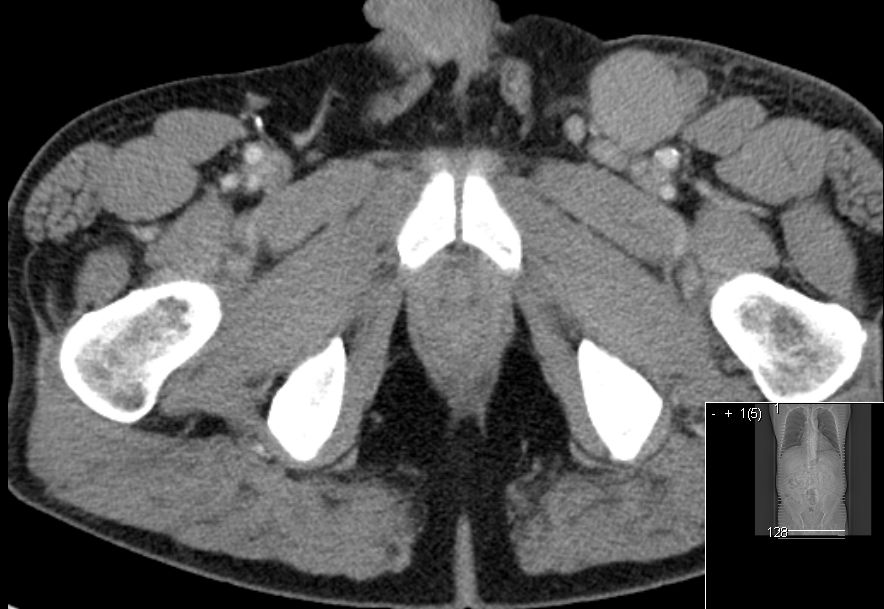

| Nach histologischer Diagnosesicherung (Referenzpathologie) Staging: CT Thorax, Abdomen, MRT, Knochenmarkspunktion | 58-jähriger Mann mit einer schmerzlosen

Schwellung der linken Leiste.![]() | ||||||||